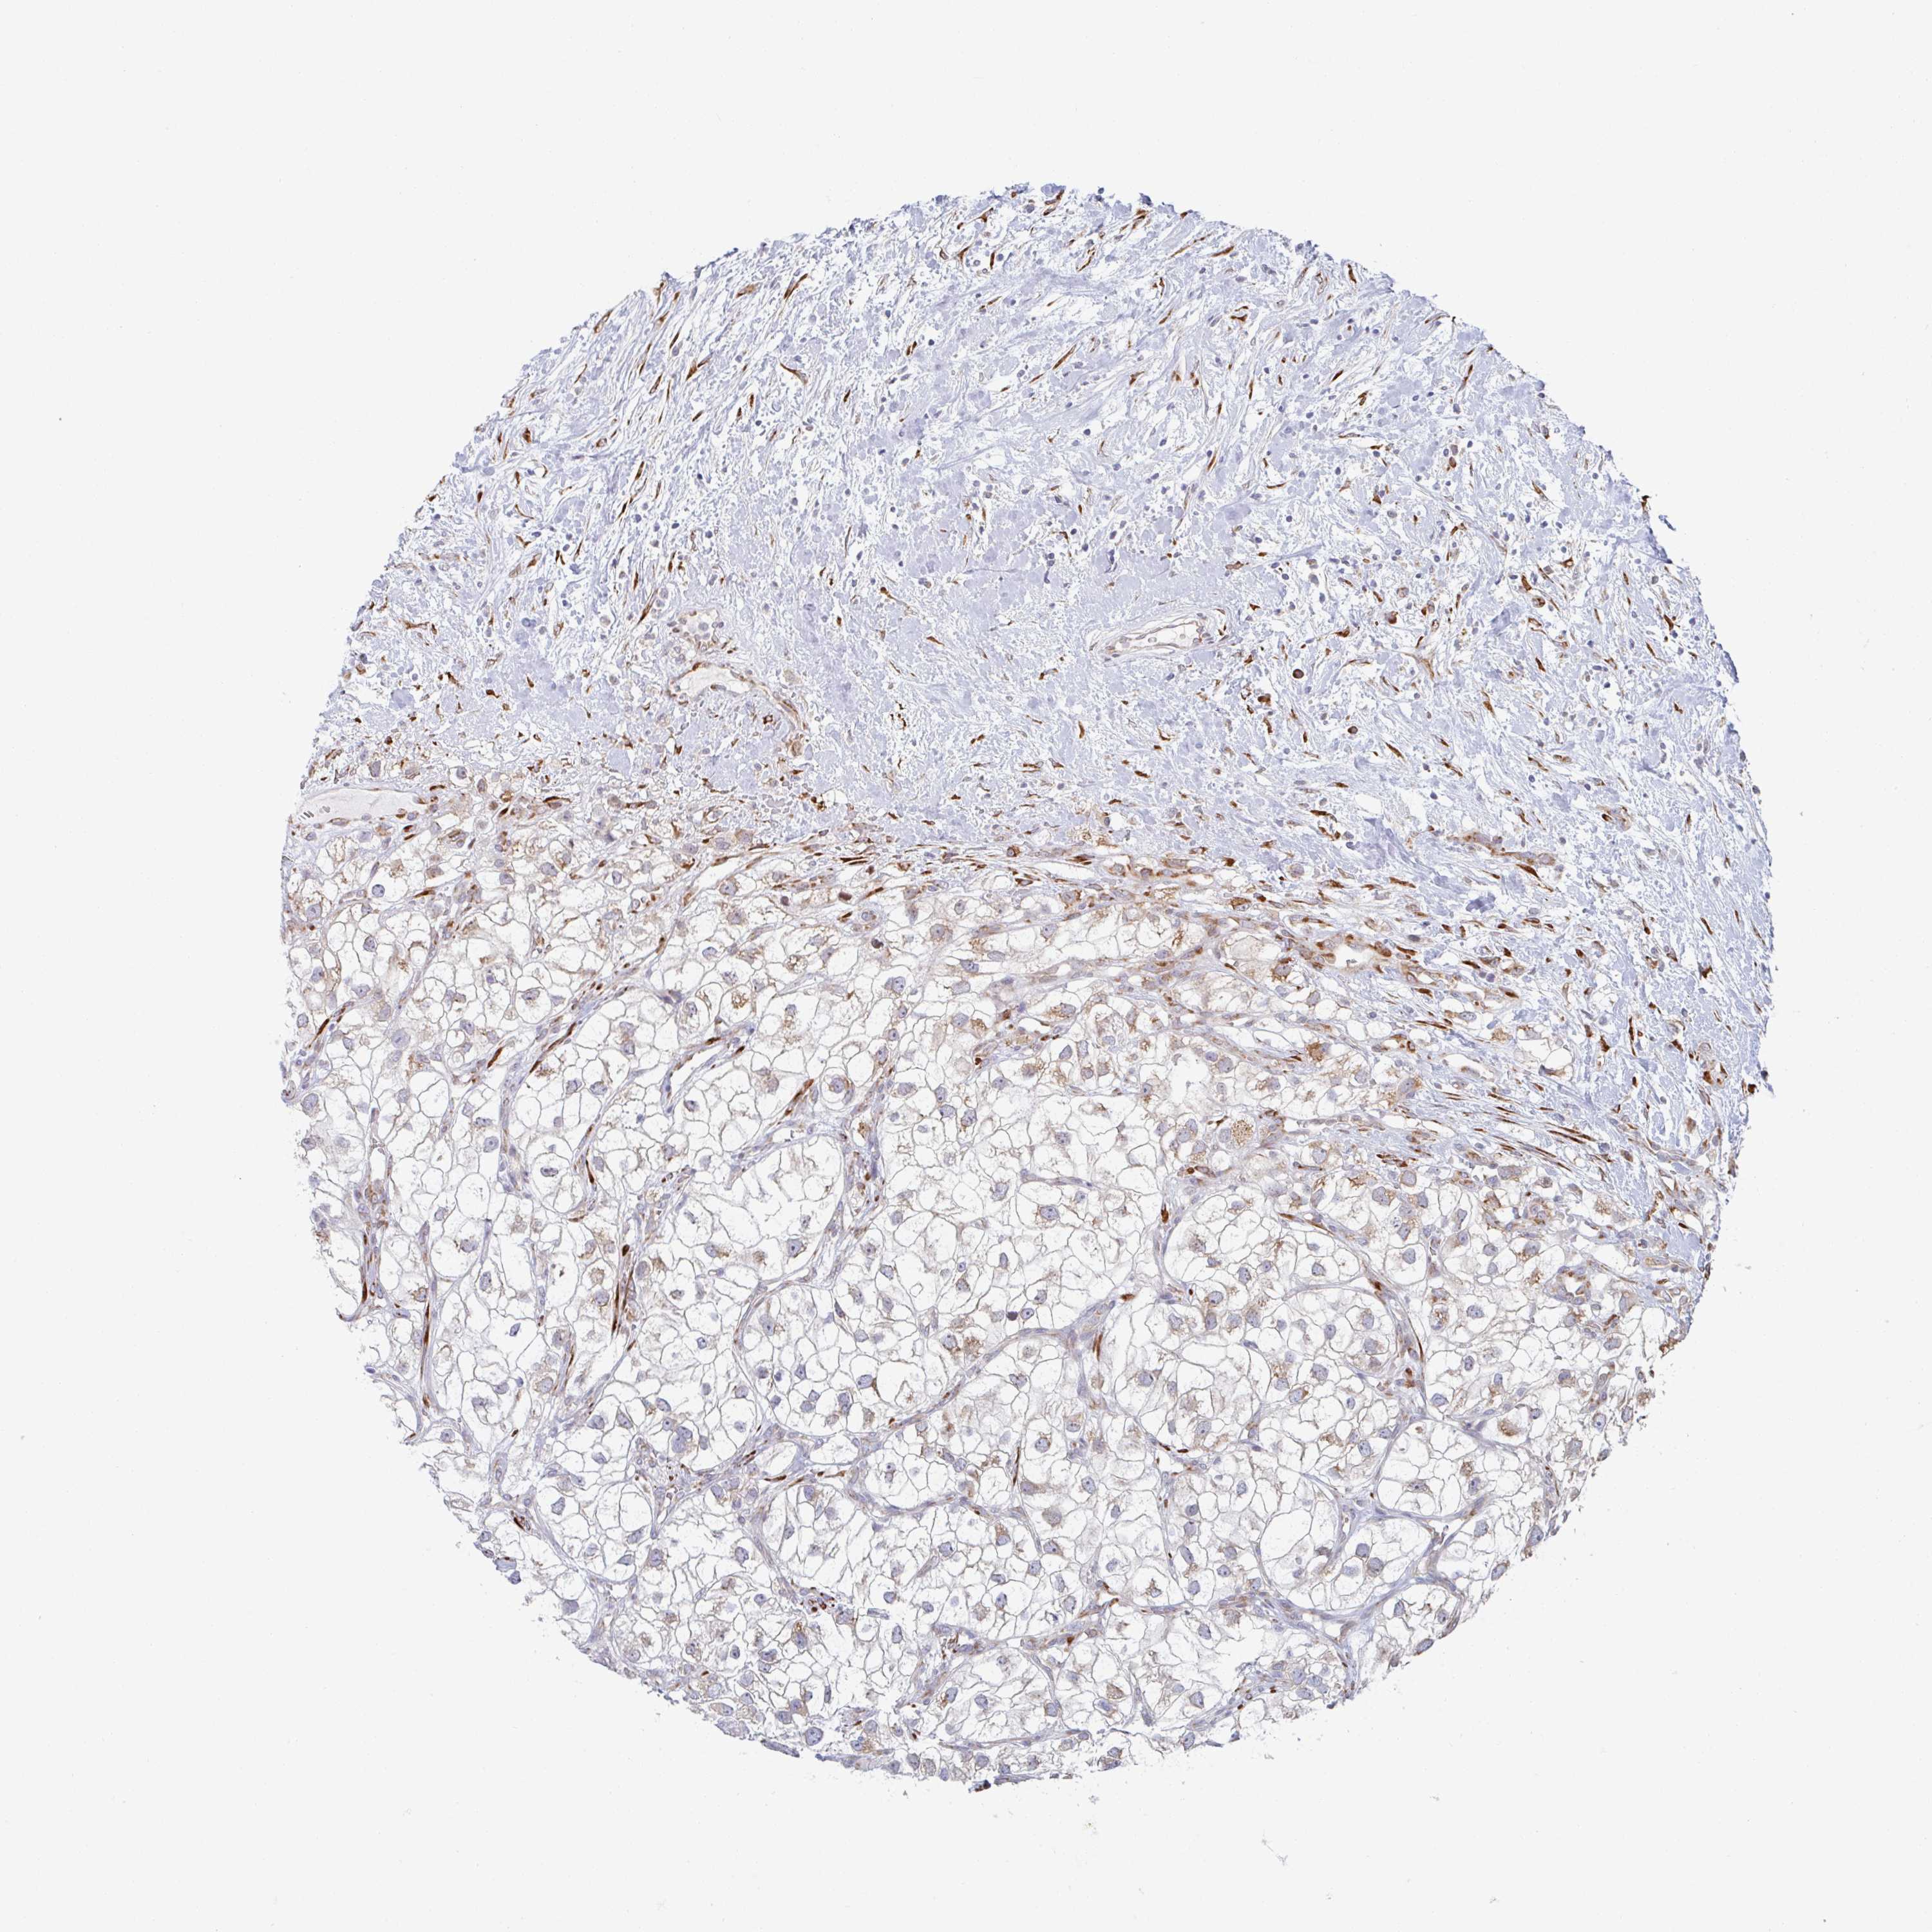

CANCER RENAL CANCER Show tissue menu

KICH TCGA KIRC TCGA KIRC VALIDATION KIRP TCGA PROTEIN RCC CPTAC PROTEIN EXPRESSION